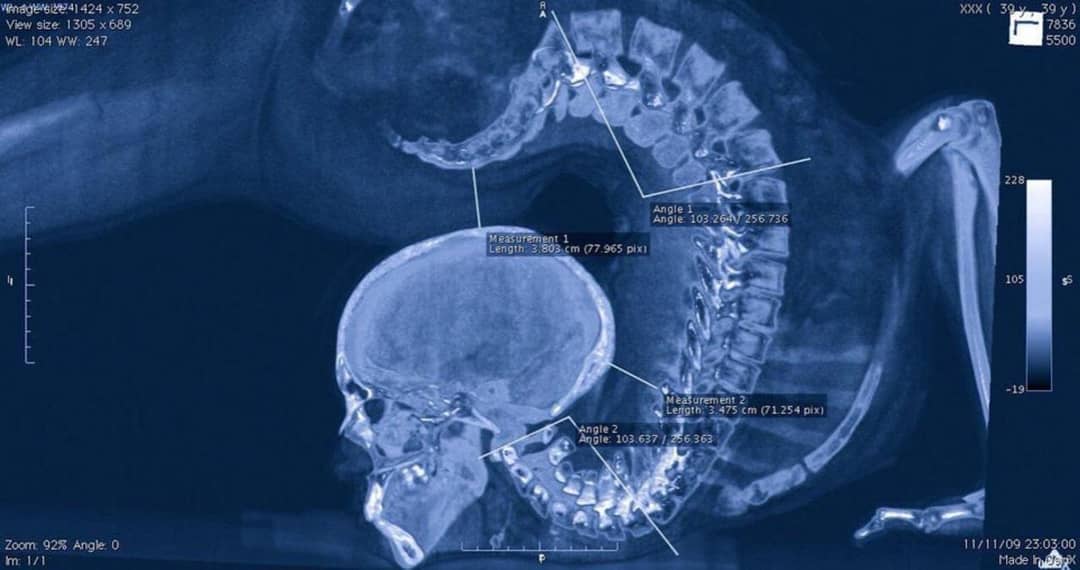

【画像】体が柔らかい体操選手のレントゲン写真、とんでもなかったwww